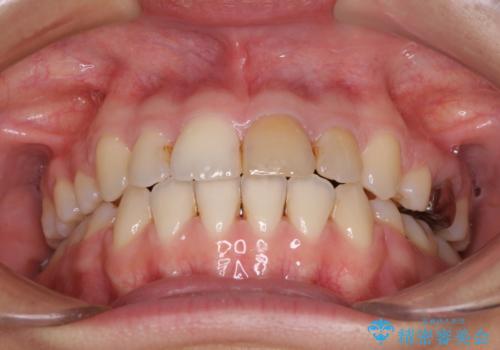

- 矯正装置

- メタルブラケット

- 治療期間

- 2年6ヶ月

- 上の八重歯を気にして来院された患者様です。

受け口傾向にあるため、上顎前歯の叢生解消とともに下顎前歯を後方へ移動させることを目的とし、上下左右の第一小臼歯4歯を抜歯することとしました。